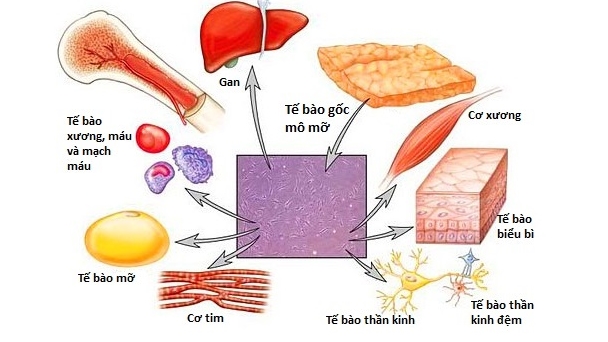

Đội ngũ có kinh nghiệm trong tế bào gốc, miễn dịch học, công nghệ sinh học, y học phân tử